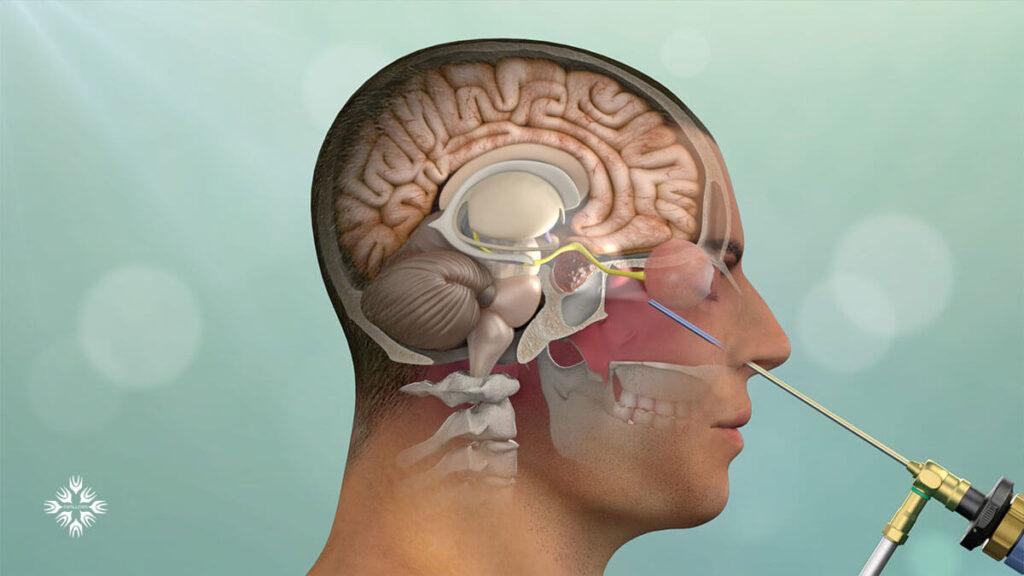

قیمت: 68٬000 تومان - دسته بندی فایل: پاورپوینتپاورپوینت مایع مغزی نخاعی (CSF)

فروش ویژه پاور پوینت حرفه ای مایع مغزی نخاعی (CSF) با تخفیف استثنایی فقط 103 هزار تومان تعداد اسلاید: 66 اسلاید